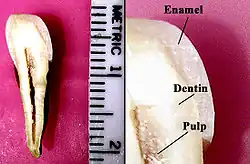

2 = Dentin

3 = Pulpencavum mit Pulpa

Die Zahnpulpa (von lateinisch pulpa ‚Fleisch‘[1]), auch Pulpa dentis, Zahnmark oder Zahnnerv genannt, füllt den inneren Teil des Zahnes, die Pulpenhöhle (Pulpencavum), aus, die von den Zahnhartsubstanzen umhüllt wird. Das Pulpencavum reicht von der Zahnkrone bis an die Spitze der Zahnwurzel(n).